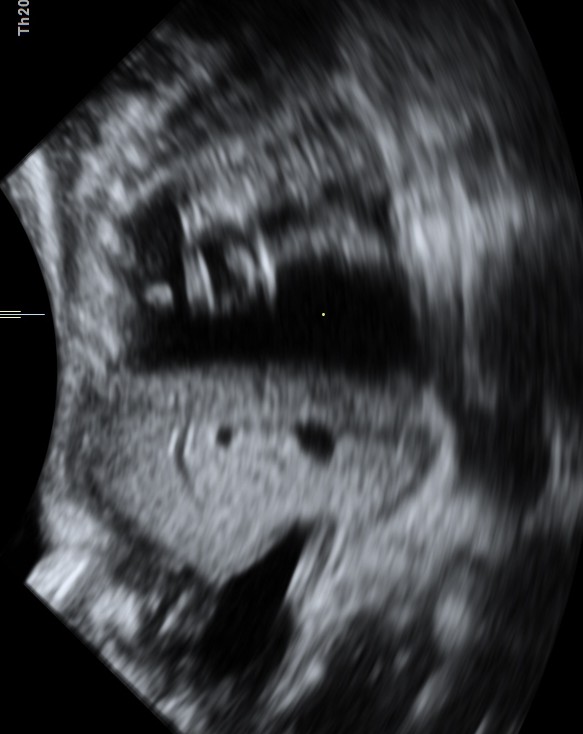

This was a 23 year old primi gravida without history of consanguinity was sent for anomaly scan at 33 weeks of gestation. Earlier two scans had not detected any anomaly at another centre.

The heart was seen in the right side of thorax . The left hemithorax showed the stomach bubble and bowel loops suggestive of Congenital Diaphragmatic Hernia .